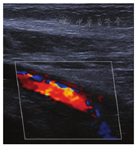

患者男,27岁,于2020年11月19日晨,被家属发现昏迷在家中(家属诉已2 d未能联系上患者),全身冰冷,四肢无活动,当时周围可见咖啡色呕吐物,室内门窗紧闭、可见烧炭的残留物,由120送入我院。查体:体温(T)36.2℃,呼吸次数(R)26次/min,血压(BP)74/35 mmHg,指氧饱和度71%。浅昏迷,巩膜及全身皮肤未见出血点,头颅无畸形,双侧瞳孔等大等圆(直径3 mm),对光反射迟钝,口唇紫绀,胸廓无畸形,双肺呼吸音粗,闻及散在湿性啰音,无胸膜摩擦音。心率(P)150次/min,律齐,未闻及杂音;全腹膨隆,腹肌稍紧张;双侧巴宾斯基(Babinski)征阴性。2020年11月19日9:00辅助检查:(1)血气分析(气管插管机械通气中、吸氧浓度FiO2:100%):酸碱度7.22、二氧化碳分压26 mmHg、氧分压154 mmHg、乳酸4.8 mmol/L、剩余碱-17.1 mmol/L、实际碳酸氢根10.6 mmol/L、COHb 16.3%。(2)血常规检查:白细胞计数19.2×109/L,红细胞计数6.43×1012/L,血红蛋白194 g/L,血细胞比容61%。(3)心肌损伤标记物检查:肌酸激酶同工酶11.2 ng/ml,肌钙蛋白1.09 ng/ml,肌红蛋白300.1 ng/ml。N-末端B型利钠肽前体15 020 pg/ml。(4)肝功能:总胆红素25.8 μmol/L,血清丙氨酸氨基转移酶137 U/L,血清天门冬氨酸氨基转移酶683 U/L,δ胆红素11.40 μmol/L。(5)凝血检查:凝血酶原时间17.0 s,国际标准化比值1.44,纤维蛋白原5.28 g/l。(6)肾功能及电解质检查:镁1.52 mmol/L,钾:3.96 mmol/L,钠147.00 mmol/L,氯108.00 mmol/L,磷2.32 mmol/L,尿素34.3 mmol/L,肌酐524.00 μmol/L,尿酸1 158 μmol/L。10:30心脏彩超检查示心脏各腔室大小正常;每搏输出量25 ml。11:00对患者头颅、胸部、腹部进行CT检查(见图1、图2):双侧基底节区片状低密度影,建议MRI检查;右下肺炎症,左下肺节段性肺不张;双肺少许纤维灶;双侧少许胸膜反应;肠梗阻。11月21日14:00下肢血管彩超:右侧股静脉、髂静脉、腘静脉管腔内异常回声,考虑漂浮血栓可能。见图3。右下肺炎症,左下肺节部他处尘肺不张,双侧少许纤维;双侧少许胸腹反应。

患者11月19日入急诊科后紧急气管插管、吸痰、呼吸机辅助通气(同步间隙指令通气模式:潮气量400 ml,呼吸频率16次/min,呼气终末正压6 cmH2O,吸入氧浓度100%)、深静脉穿刺置管、补液、留置尿管等,患者指氧饱和度上升至100%,血压98/62 mmHg。完善辅助检查后收入重症医学科治疗。入重症医学科后诊断为ACOP,予呼吸机支持,禁食水,胃肠减压,血压稳定后予以甘露醇、呋塞米降颅内压,抗感染,抑酸及营养支持等治疗。患者入院2 h后出现发热及全身抽搐,立即予以咪达唑仑5 mg/h联合丙戊酸钠0.8 g/d微量泵入抗癫痫(床旁脑电图监测下调整米达唑仑剂量)。住院期间因患者右下肢较左侧肿胀于11月21日行床旁下肢血管彩超考虑右侧股静脉、髂静脉、腘静脉漂浮血栓可能,复查D-二聚体升高。给予患者安置滤网,低分子肝素皮下注射抗凝。因患者存在气管插管、有创呼吸机及癫痫发作,无法行高压氧治疗。积极治疗3 d后患者仍昏迷,但生命体征稳定,腹部膨隆逐渐缓解,复查CT提示肠梗阻明显缓解,序贯胃管注入丙戊酸钠抗癫痫。第5天患者对疼痛刺激有反应,脑电图监测未见癫痫波,预计昏迷时间较长,予以气管切开后停用呼吸机,使用导管内给氧维持氧合,开始行高压氧治疗。第12天予拔除气管切开导管后改鼻导管吸氧,患者持续浅昏迷状态,第15天转康复科继续康复及高压氧治疗。经过2个疗程高压氧治疗(共20次),患者拔除气管切开导管,自主呼吸平稳,但意识仍为浅昏迷,共住院32 d后自动出院。

根据患者表现及血中COHb浓度将ACOP分为轻、中、重度中毒,相比轻度CO中毒患者,中重度CO中毒患者由于血内HbCO含量高,相关脏器特别是神经系统缺氧更加严重,导致器质性损害更加明显,预后更差。本例患者虽COHb浓度仅为16.3%,但出现昏迷,伴发休克、呼吸衰竭,仍考虑为重度ACOP,COHb浓度不高,考虑中毒至发现间隔时间较长,而炭火熄灭后未再继续吸入CO,COHb浓度逐渐下降所致。本例患者为青年男性,既往无静脉血栓基础病史,ACOP后出现了深静脉血栓,考虑是由于ACOP后机体缺氧使血管内皮细胞损伤、脱落,血小板活性增加,启动血小板黏附、聚集并黏附于血管壁所致。而患者在中毒后较长时间才被发现,近2 d未进食进饮,机体存在脱水情况、血常规中白细胞、红细胞、血红蛋白均远高于正常值,电解质血钠高于正常值提示血液浓缩、凝血功能检查示纤维蛋白原升高,提示血液呈高凝状态,也促进了血栓形成[5,6]。患者同时出现了肠梗阻(CT提示),检索未见相关病例报道。考虑出现肠梗阻与ACOP后中枢神经系统损伤,通过直接或间接神经联系和神经递质作用于肠神经,胃肠道功能调控受损;缺氧、脑水肿后自主神经系统功能障碍,副交感神经兴奋性降低,腺体分泌受抑制,胃肠道移行性复合运动(MMC)减少或缺乏,影响胃肠内容物的转运和排空等密切相关[7]。